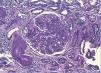

Se inició tratamiento depletivo con diuréticos, inhibidores de la enzima de conversión de la angiotensina (IECA) y antagonistas de los receptores de angiotensina II (ARAII), estatinas, heparina de bajo peso molecular, y se recomendó mejorar el control glucémico. Debido a la hidronefrosis del riñón izquierdo provocada por un síndrome de la unión pieloureteral se realizó pieloplastia y se colocó una nefrostomía percutánea en el riñón izquierdo. A pesar de estas medidas el paciente requirió nuevos ingresos hospitalarios por descompensación del síndrome nefrótico, con incremento de la creatinina plasmática a 2,5-3 mg/dl y persistencia de la proteinuria nefrótica, motivo por el que se decide iniciar programa de hemodiálisis. Aunque la sospecha inicial fue de ND, estando el paciente en hemodiálisis persistió el mal control volumétrico y con parámetros bioquímicos de actividad del síndrome nefrótico decidimos realizar una biopsia renal para descartar una glomerulopatía asociada. Los hallazgos de biopsia fueron: 12 glomérulos por plano de corte, cinco de ellos completamente esclerosados. Todos los glomérulos estudiados mostraban una expansión mesangial con formación de nódulos acelulares (Kinmelstein-Wilson). La inmunofluorescencia fue negativa. En el intersticio se observó una fibrosis moderada con focos de atrofia tubular asociada. El componente vascular mostró una llamativa hialinosis de su pared, siendo el diagnostico anatomopatológico final compatible con una glomeruloesclerosis difusa (figura 1) y nodular (figura 2), con sustrato morfológico de enfermedad diabética.

Figura 1. Técnica de PAS (x20 aumentos): glomeruloesclerosis difusa con hialinosis de la arteriola eferente e intensa hialinosis de vasos de mediano calibre.